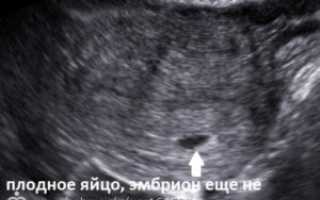

На очень раннем сроке зародыша в плодном яйце еще не видно, и это норма. А вот с пяти недель эмбрион уже должен визуализироваться. В случае, если эмбриона не видно, через 1-2 недели назначают повторное исследование. Если же и на этот раз нет ни эмбриона, ни сердцебиения, говорят об анэмбрионие. В таком случае женщине необходимо сделать чистку.

Так на УЗИ выглядит пустое плодное яйцо.

Пустое плодное яйцо – это по сути беременность, которая не начала развиваться. Процесс развития прекратился еще до этапа формирования эмбриона. Причин такого нарушения достаточно много.

На ранних сроках крайне сложно выявить пустое плодное яйцо. Так как размеры эмбриона очень малы и его можно просто не заметить. Только по прошествии 5 недель, появляется возможность определить отсутствие плода.

Только на шестой неделе беременности пустое плодное яйцо можно диагностировать с помощью УЗИ. Оно проводится в любом случае, чтобы определить месторасположение плода, а также исключить внематочную беременность.